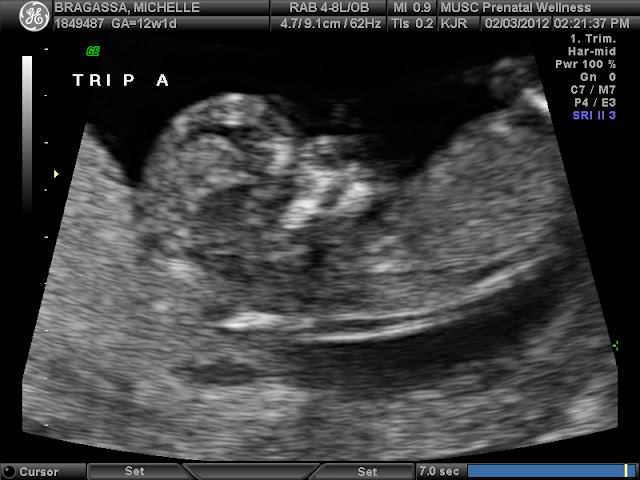

February 3, 2012 (12 weeks 1 day) - We had our first appointment with the Maternal Fetal Specialist at the High Risk Clinic at MUSC down in Charleston.  We are so blessed to live where we do!  They have a huge team of highly trained doctors who do a fellowship after their residency to specialize even further into the Ob/Gyn world.  In fact, one of the country's top MFS (maternal fetal specialists) who specifically concentrates on higher order multiples is here at MUSC.  The funny thing was that right after we found out it was triplets, I ordered a book off of Amazon that was highly recommended to parents of triplets.  I brought it with me to my first appointment only to find out that my doctor was one of the co-authors.  Anyway, enough about the doctors (although they are super important!)!  Let's talk about the babies!  At this appointment, we were able to see our little babies and they no longer looked like gummy bears!  They actually looked like babies:)  It was amazing how much the ultrasound tech could tell us about the babies...for instance...we found out that they all had brains that were divided into two hemispheres, all had 2 arms and 2 legs, their bones were beginning to form, and they all had properly functioning kidneys, and they are all fraternal.  We could even see them moving around a little bit!  At this appointment, we also learned a whole heck of a lot about what to expect with a triplet pregnancy.  In all honesty, in some ways it's just like any other pregnancy, but in a lot of ways, it's waaaayyyy different.  Here are some of the things we found out: